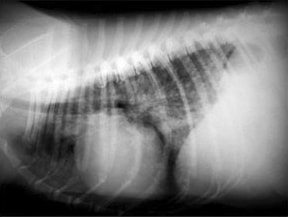

A・B:猫の肥大型心筋症による胸水の貯留 正面像と側面像

C:猫の肥大型心筋症による肺水腫 側面像

D:Cの肺水腫治癒後 側面像

通常、心拡大を認めないことも多く、胸部レントゲン単独での発見は困難ですが、拡張相に移行すると心拡大が認められるようになります。呼吸困難を伴う肥大型心筋症の場合、肺水腫や胸水などの所見が認められることがあります。